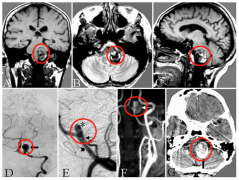

INC国际教授高度疑难脑动脉瘤成

术前磁共振扫描显示部分血栓形成的VA-PICA动脉瘤,并压迫脑干(...